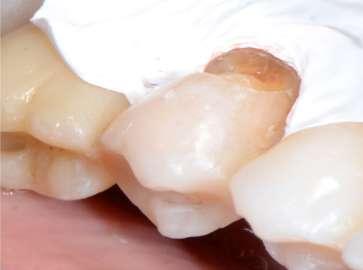

Trattamento dell’osteonecrosi mandibolare da bifosfonati

Laureato in Medicina e Chirurgia nel 1986 e specializzato in Odontostomatologia presso l’Università di Torino nel 1990, è specializzato in implantologia e chirurgia orale, implantologia a carico immediato e nel posizionamento di impianti zigomatici a carico immediato

Ancora oggi non esiste un protocollo univoco di trattamento di questo tipo di complicanza e le motivazioni di questa assenza risiedono nella enorme variabilità della casistica tra paziente e paziente.

Ci sono però dei punti fermi su cui è ormai scontato che si debba fondare il proprio operato: pulizia, garantita dalla detersione profonda con l’utilizzo del PiezoClean®, e stimolazione alla guarigione indotta dal PRGF®3

I bifosfonati orali sono largamente utilizzati per la gestione clinica di un cospicuo numero di patologie come, per citarne alcune, il morbo di Paget, l’osteoporosi post menopausa e, ancora, le metastasi ossee.

Questi farmaci esplicano la loro efficacia nella limitazione importante del turn over osseo e rappresentano ancora una prima scelta dei trattamenti orientati alla ridensificazione ossea e alla limitazione della proliferazione di cellule alterate.

Il rischio di osteonecrosi della mandibola da farmaci nei pazienti con osteoporosi che assumono bifosfonati orali è estremamente basso ed è paragonabile alla prevalenza nella popolazione generale (circa 1 caso per 100 000 pazienti anno)1

La BRONJ è identificabile come una zona priva di vascolarizzazione, in cui il tessuto osseo appare necrotico, localizzabile nell'area maxillo-facciale; essa può determinare o meno una esposizione ossea.

La correlazione tra l’assunzione di bifosfonati orali e la comparsa di necrosi mandibolare è certa, così come certa è l’urgenza con cui è necessario intervenire su questo tipo di complicanza. Intercettare precocemente la problematica è possibile attraverso il follow-up. Appurata la presenza di una necrosi ossea, è indispensabile fornire all’organismo del paziente le corrette molecole antibiotiche per il trattamento e la prevenzione delle infezioni del sito chirurgico. Le complicanze di un mancato trattamento sono infatti gravi (es. compromissione del nervo alveolare, frattura di mandola, comunicazioni bucco-sinusali)2

Nel corso di questo articolo si vuole presentare l’approccio diagnostico terapeutico basato proprio sul rispetto di questi concetti fondamentali.

La paziente è una donna di 73 anni, in terapia con denosumab e corticosteoidi per il trattamento dell’artrite reumatoide.

È giunta per un ascesso con presenza di fistola drenante nel 4° quadrante ed è stata sottoposta a CBCT che ha rivelato la presenza di una necrosi mandibolare nella zona interessata dalla problematica ascessuale.

La necrosi, in estensione da 4.5 a 4.7, era stata precedentemente trattata con riabilitazione su impianti; sulla base di ciò è stata impostata la terapia antibiotica combinata con Amoxicillina+ac. Clavulanico e metronidazolo.

nio venoso della paziente, per il prelievo ematico necessario alla produzione del PRGF, l’apertura della bocca del soggetto stesso che, in questo caso, risultava piuttosto limitato. La progettazione chirurgica è utile anche per scegliere preventivamente il tipo di strumentazione che verrà utilizzata durante l’intervento.

La paziente è stata sottoposta a prelievo venoso per la produzione del PRGF. In seguito è stato usato anestetico locale in

autoclave, possiede una conformazione tale da adattarsi alla cresta e possiede capacità adesive che permettono di creare un effetto cavitazione al suo interno. È eccellente per la detersione degli alveoli post estrattivi, ma anche per zone più ampie, grazie alle diverse misure a disposizione.

La progettazione dell’intervento deve obbligatoriamente tenere in considerazione alcuni aspetti: l’estensione della lesione, misurabile tramite software, il patrimo-

tubofiala odontoiatrica a base di articaina 1:100000 con adrenalina, somministrata previa rilevazione dei parametri vitali.

Mediante l’esecuzione di un lembo trapezoidale è stato possibile avere accesso all’intera zona necrotica, con buona visibilità del campo, nonostante la scarsa apertura buccale.

Dopo aver scollato ed esposto la zona, mediante l’uso dello strumento ultrasonico si è rimossa la porzione necrotica.

Per questa azione di toelettatura sono stati adoperati gli inserti Esacrom ES052XGT e ES010T.

Verificata la completa rimozione del tessuto malato e appurato il ripristino della vascolarizzazione del sito, è stato ulteriormente deterso mediante una applicazione della durata di 60 secondi dell’inserto PIEZOCLEAN, il cui utilizzo produce detersione profonda della zona su cui viene applicato. Infatti il dispositivo, in silicone sterilizzabile in

Al termine della toelettatura, sono state posizionate le due frazioni di PRGF e si è effettuata sutura interna con Vycril 4/0 ed esterna con seta 4/0.

L’immagine finale mostra lo stato della mucosa a distanza di 1 anno.